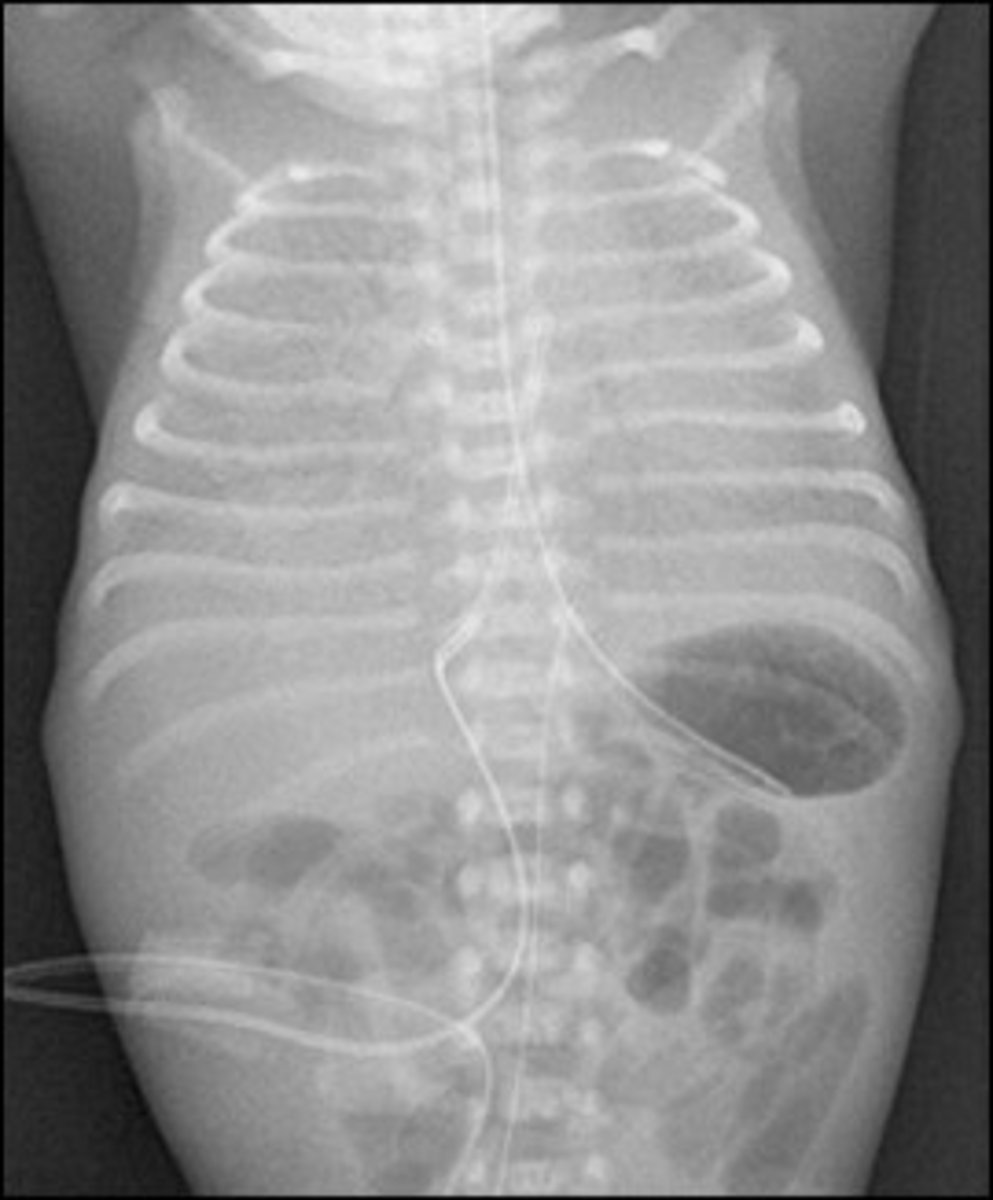

Necrotizing enterocolitis

- What do you see on X-ray? pneumocystis intestinal (air in bowel wall)

- Treatment? NPO, TPN (if nec), antibiotics and resection of necrotic bowel

- Risk factors? Premature gut, introduction of feeds, formula.

A 5 day old former 33 weeker develops bloody diarrhea

- What do you see on xray?

- Treatment?

- Risk factors?